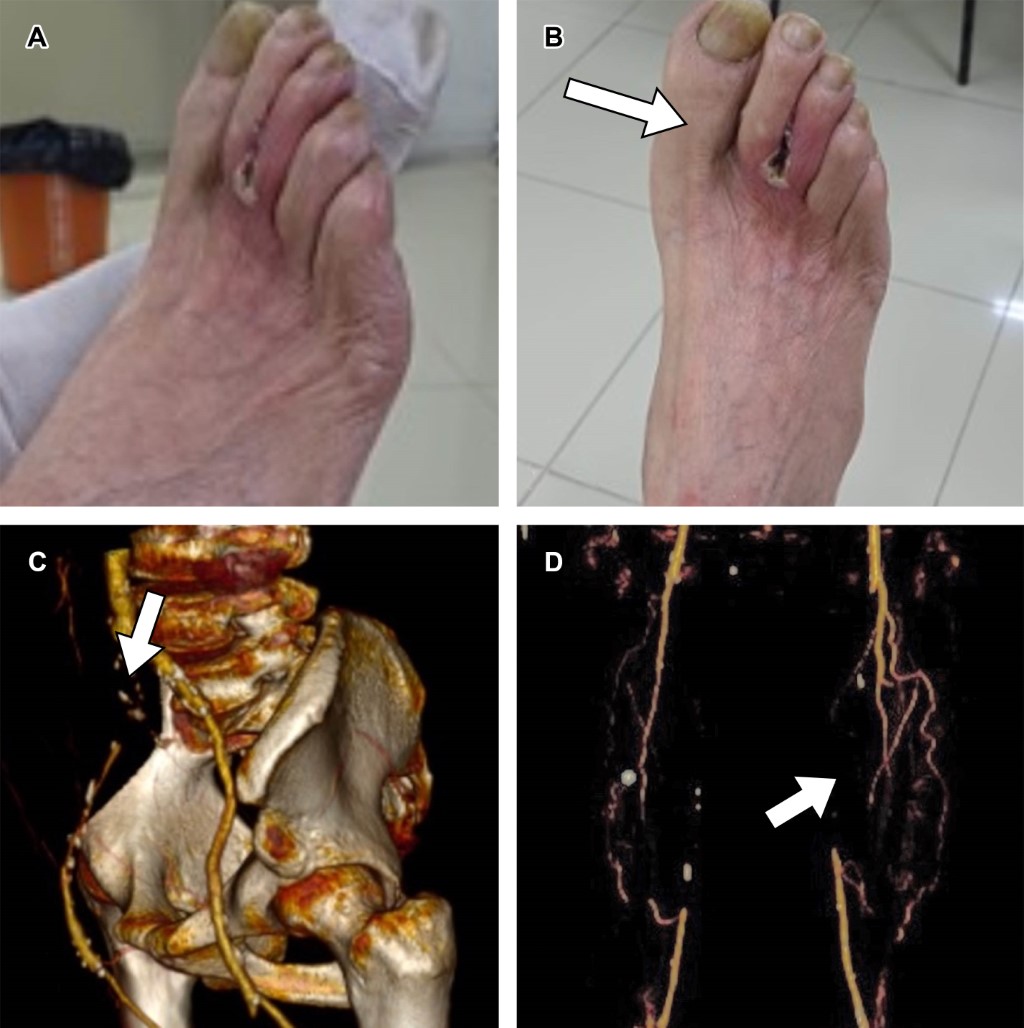

Al examen físico: miembro pélvico izquierdo sin lesiones isquémicas, sin embargo, no presenta pulsos desde región femoral hasta región pedia. Miembro pélvico derecho con presencia de poiquilotermia, atrófico, necrosis seca interdigital entre el segundo y tercer ortejo sin presencia de pulsos desde región femoral hasta región pedia (Figura 1A y B). TAC mostró evidencia de enfermedad aortoiliaca según la clasificación Trans-Atlantic Inter-Society Consensus (TASC) D (Figura 1C y D).

Figura 1